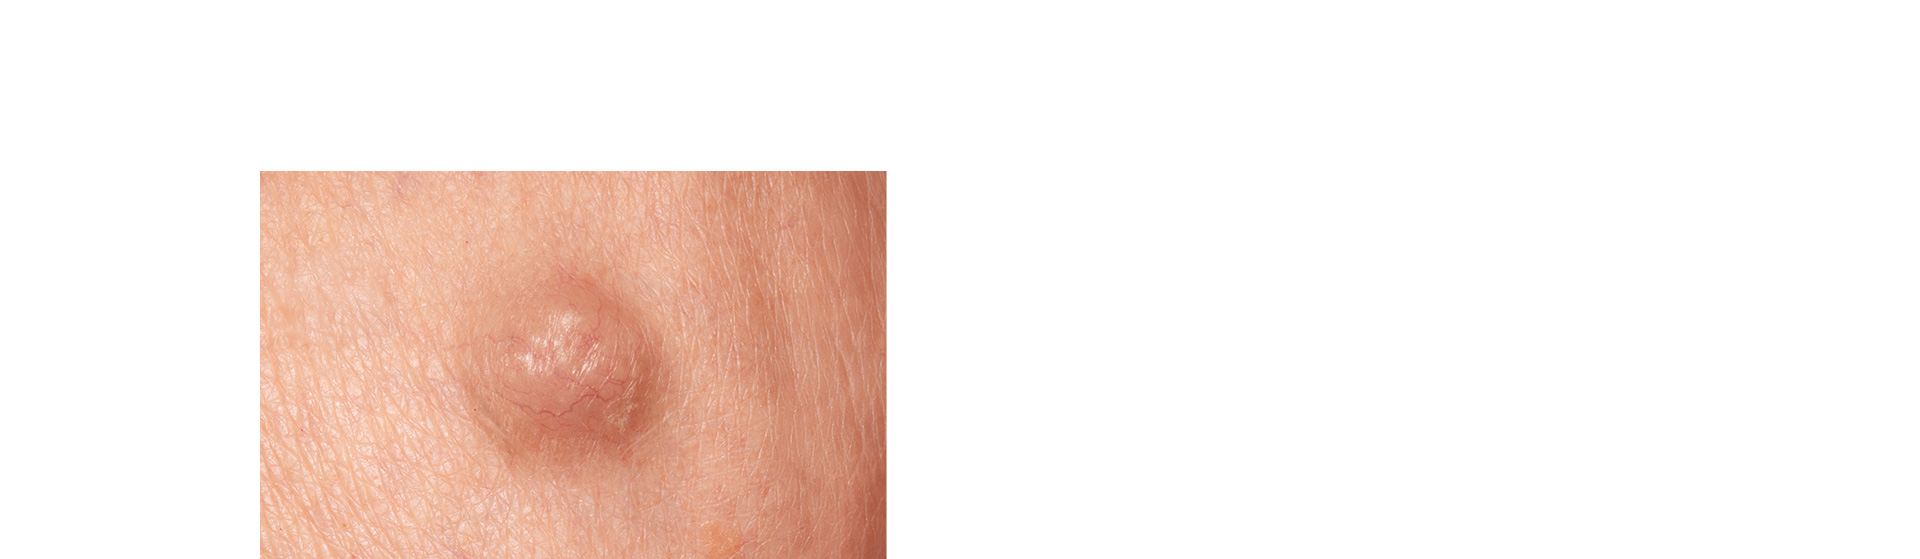

방치하지말고 제거하자!양성종양수술

피부 양성종양은 몸의 세포가 비정상적으로 자라나며 발생하는

일종의 피부 혹으로 목뒤, 등, 팔, 어깨, 허벅지 등 다양한 부위에 발생합니다.

악성과 달리 반드시 제거가 필요하지는 않지만

방치할 경우 내부가 감염되어 염증이 생기거나 크기가 커져

통증을 유발할 수 있기 때문에 바로 제거하는 것이 좋습니다.